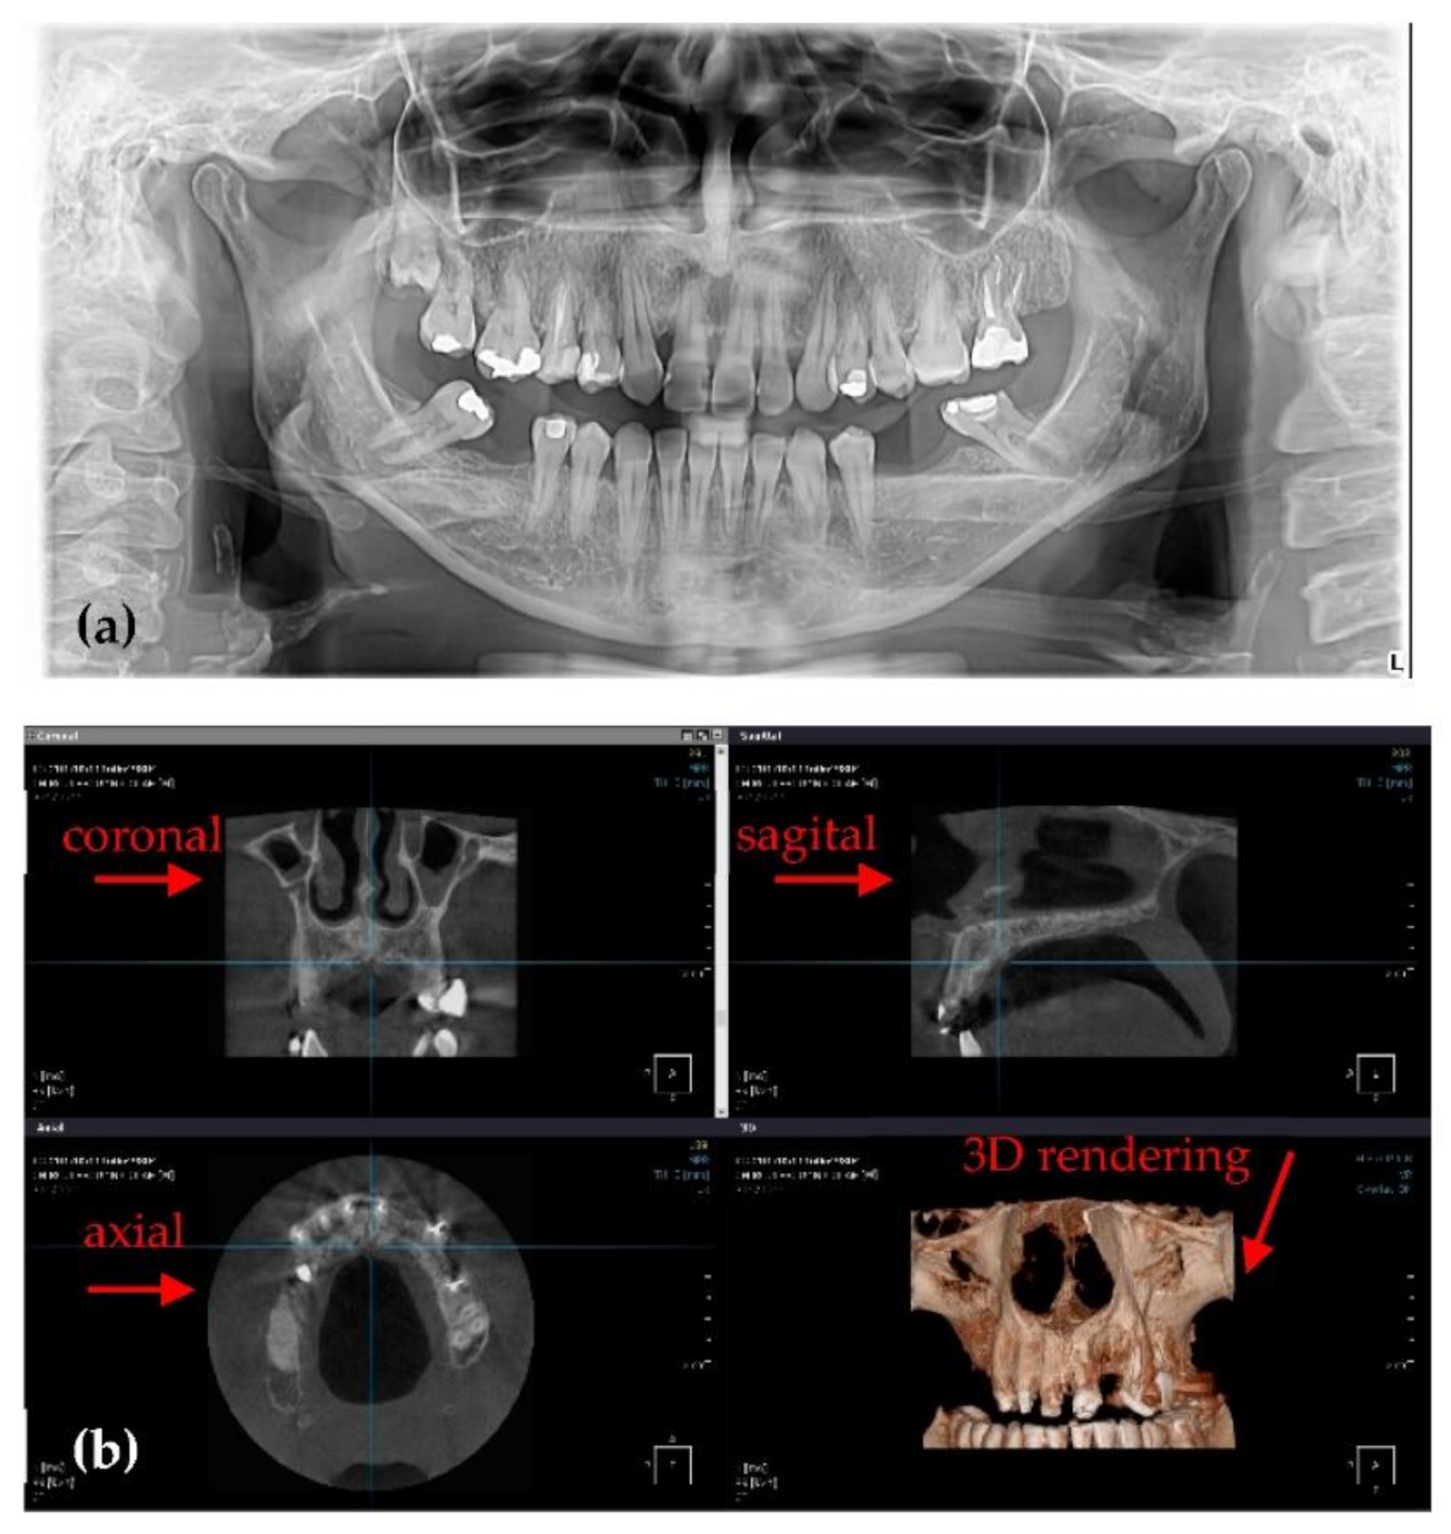

3.4. Differences Between the Planmeca and the Soredex System

| Radiograph | Characteristics | Planmeca | Soredex | |

|---|---|---|---|---|

| Panoramic | Anode voltage (kV) | 68 to 73 | 70 to 75 | |

| Current intensity (mA) | 8 to 11 | 8 to 11 | ||

| Exposure time (s) | 14.990 | 16 | ||

| DAP (mGy×cm2) | 97 to 117 | 175 to 250 | ||

| Effective Dose (µSv) | 7.8 to 9.2 | 14 to 20 | ||

| Pixel side (µm) | 127 | 100 | ||

| Total 3D CBCT | Anode voltage (kV) | 90 | 85 to 90 | |

| Current intensity (mA) | 11 to 14 | 6 to 10 | ||

| Exposure time (s) | 5 | 6 to 9 | ||

| DAP (mGy×cm2) | 691* | 749.5 ** | ||

| Effective Dose (µSv) | 86.4* | 93.7 ** | ||

| Voxel side (µm) | 150 | 200 | ||

| Base diameter (mm) | of the investigated volume | 110 | 150 | |

| Height (mm) | 80 | 80 | ||

| Panoramic | Planmeca and Soredex | Radiation dose is almost 50% smaller for Planmeca. Resolution is lower (127 µm) for Planmeca than for Soredex (100 µm). Images produced by Soredex have a lower contrast and sharpness even if they have better resolutions. |

| 3D CBCT | Planmeca and Soredex | Smaller exposure time (5 versus 9 s), smaller radiation dose (with at least 10 µSv), and smaller voxel side (with 25%) for Planmeca, which means better resolution, contrast, and image quality. The covered volume is larger for Soredex. |